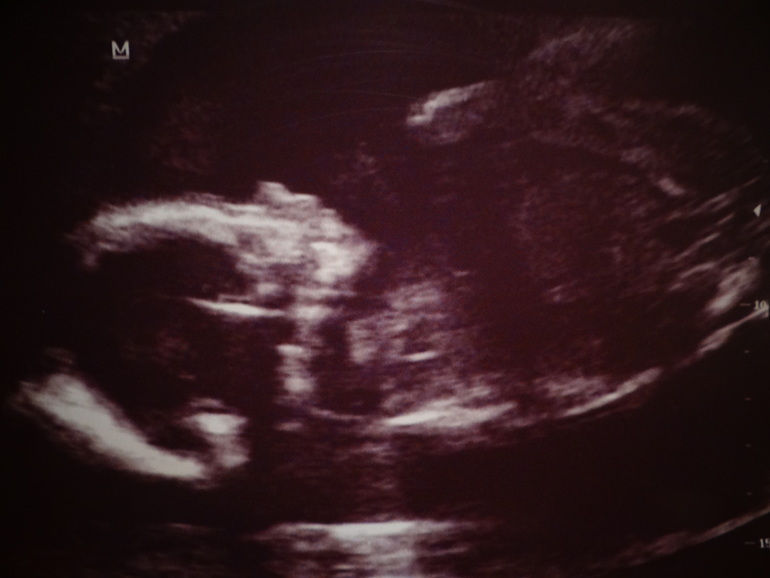

УЗИ прошло очень позитивно и плодотворно.

Еще раз, но уже со 100% гарантией, нам сказали что у нас доча

С дочей все хорошо, идеальные показатели (как сказал врач, как в книжках). ПДР поставили с 26.04 по 01.05.

ВОТ НАША КРАСОТА